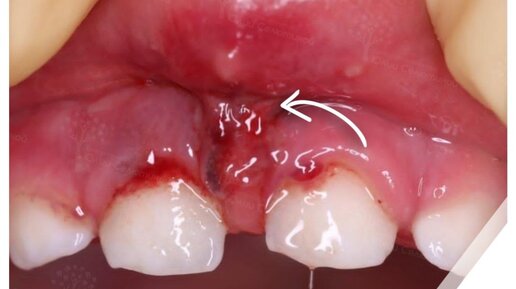

Ребёнок рассёк уздечку: что делать?

Иногда случаются такие травмы, при которых .... Ничего. Делать. Не нужно. Доктор, вы меня пугаете, как же так? Ситуация следующая: ребенок упал и рассек уздечку верхней губы. Она просто немного оторвалась в месте ее прикрепления к десне. Да, есть ранка. Да, нужно обработать ее антисептиком (Мирамистин, Хлоргексидин). Да, потом нужно будет мазать заживляющими средствами (Холисал, облепиховое масло, Асепта гель, Солкосерил дентальный). Но ничего глобального в стоматологическом, ортодонтическом и даже хирургическом плане делать не нужно...